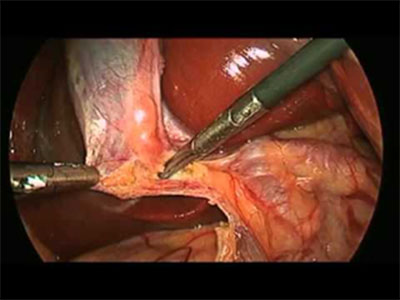

Cholecystectomy is typically performed using laparoscopic (keyhole) surgery, which involves four small incisions. The procedure takes about one hour under general anaesthesia. The gallbladder is retracted, and the cystic duct and artery are clipped and divided to remove the organ. After the gallbladder is removed, it is sent to a pathologist for examination to check for any signs of inflammation.